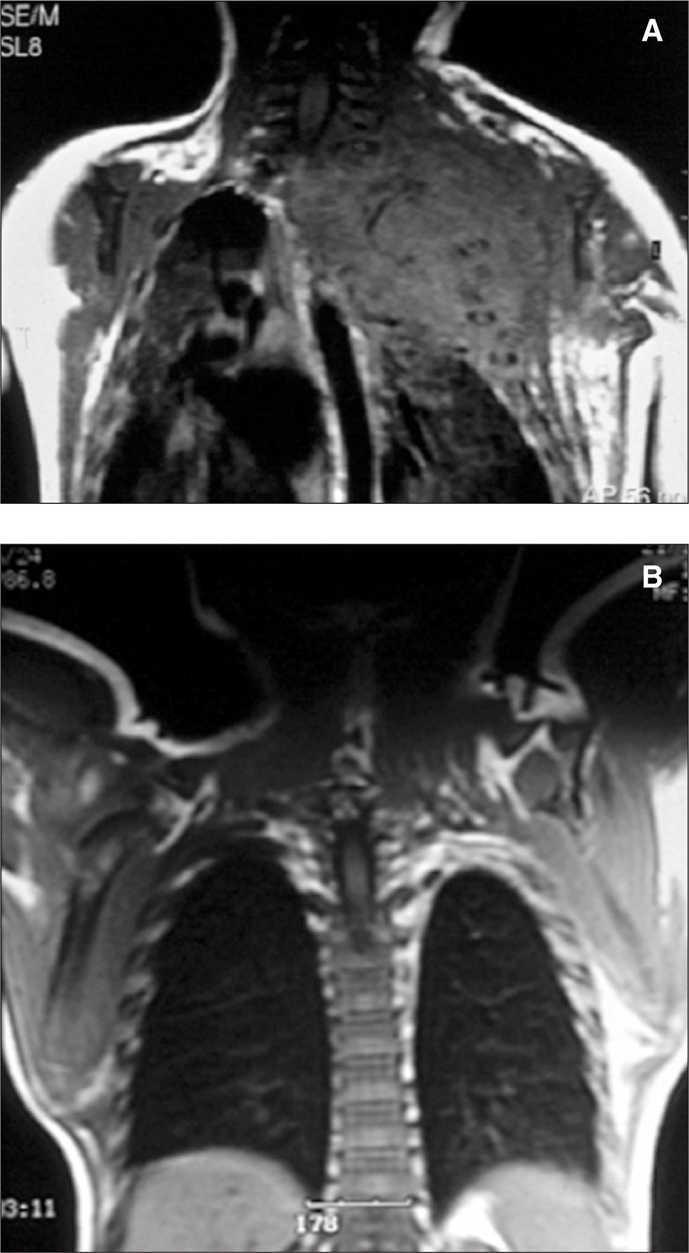

Caso 2

Recién nacido con insuficiencia respiratoria grave, hemotórax que precisó drenaje pleural y gran tumoración en la parte superior del hemitórax izquierdo (fig. 2). La analítica muestra coagulopatía compatible con síndrome de Kasabach-Merritt (trombocitopenia intensa de 7.000 plaquetas/μl y elevación del dímero-D hasta 2 ng/ml). Se inició tratamiento con corticoides a 3 mg/kg/día sin obtener respuesta a los 5 días por lo que se inició la administración de interferón α2a a 3 millones de U/m 2 subcutáneo, siendo entonces la respuesta inmediata con una elevación progresiva de la cifra de plaquetas y una mejoría significativa en los parámetros ventilatorios con desaparición del hemotórax.

Figura 2.Caso 2.

A los 9 meses la RM mostraba una desaparición casi completa de la tumoración (fig. 2) y 8 años después el paciente sólo presentaba un leve síndrome de Claude- Bernard-Horner residual.